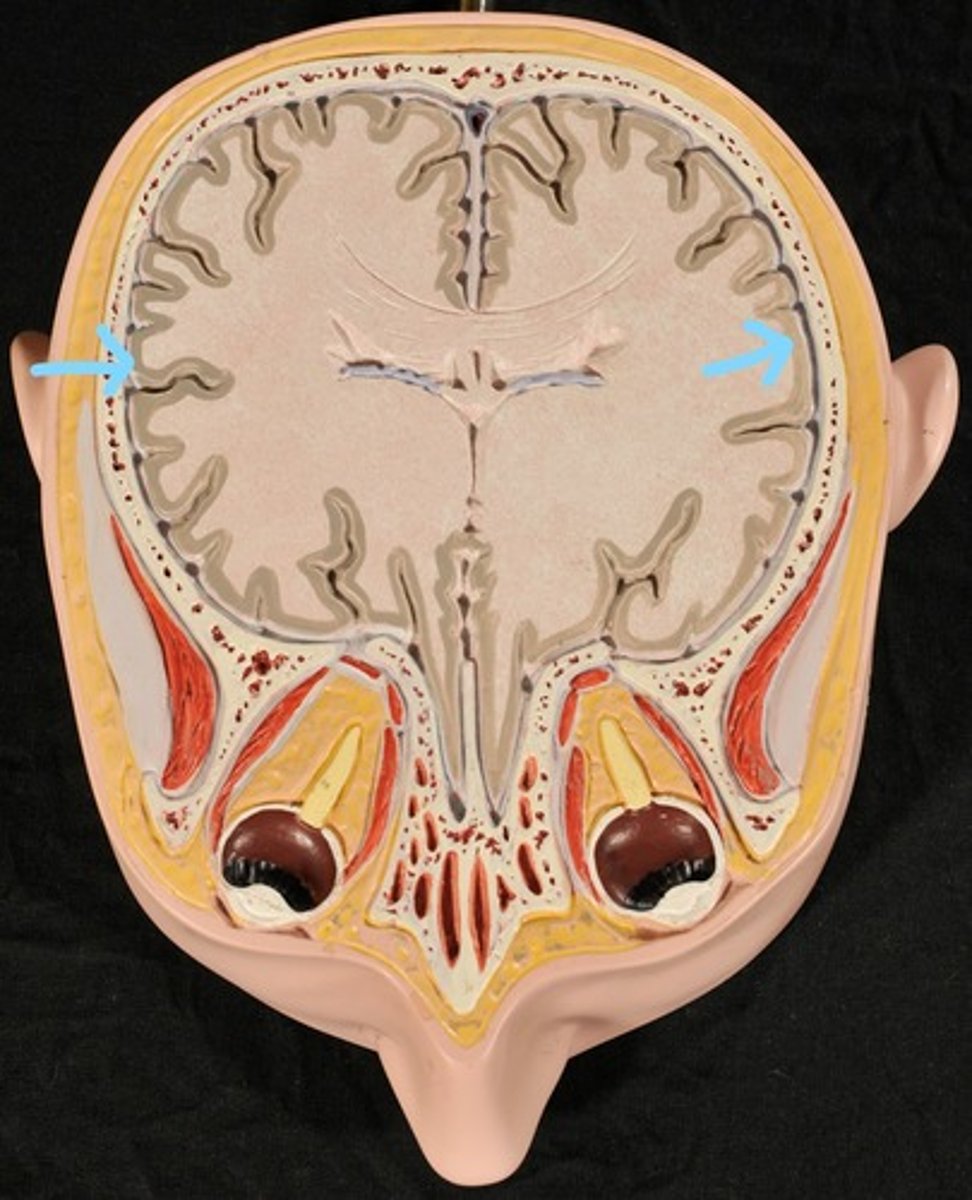

Cerebral Cortex (gray matter) (Slice 2)

Cerebral Medulla (white matter) (Slice 2)

Right & Left Parietal Lobes (Slice 2)

Third Ventricle (Slice 2)

Right & Left Lateral Ventricles (Slice 2)

Choroid Plexus (blue) (Slice 2)